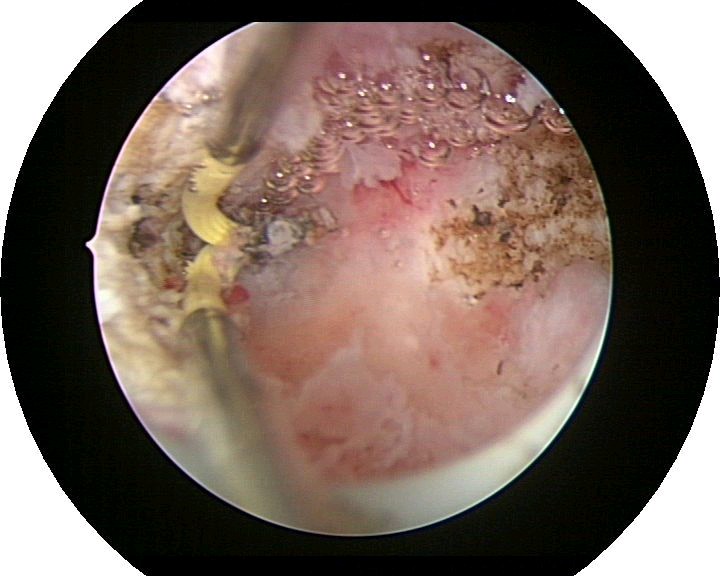

患者35岁,G4P0,2011年4月因继发不孕、月经减少2年,行宫腔镜探查,发现宫腔广泛重度粘连,单极电切分粘,恢复宫腔形态,显露双侧输卵管开口,放置节育环一个,术后月经恢复正常。2011年9月行宫腔镜二探并取环,O型环部分嵌顿,分离残留粘连,宫腔形态正常,双侧输卵管开口可见,同时行腹腔镜下左侧卵巢囊肿剥除术,术中通液双侧输卵管通畅。术后病人及爱人外出旅行,2个月后自然妊娠至足月,2012年7月要求我到其住院医院为其剖宫产,胎盘粘连,出血较多,手术顺利。现49岁,G5P1。